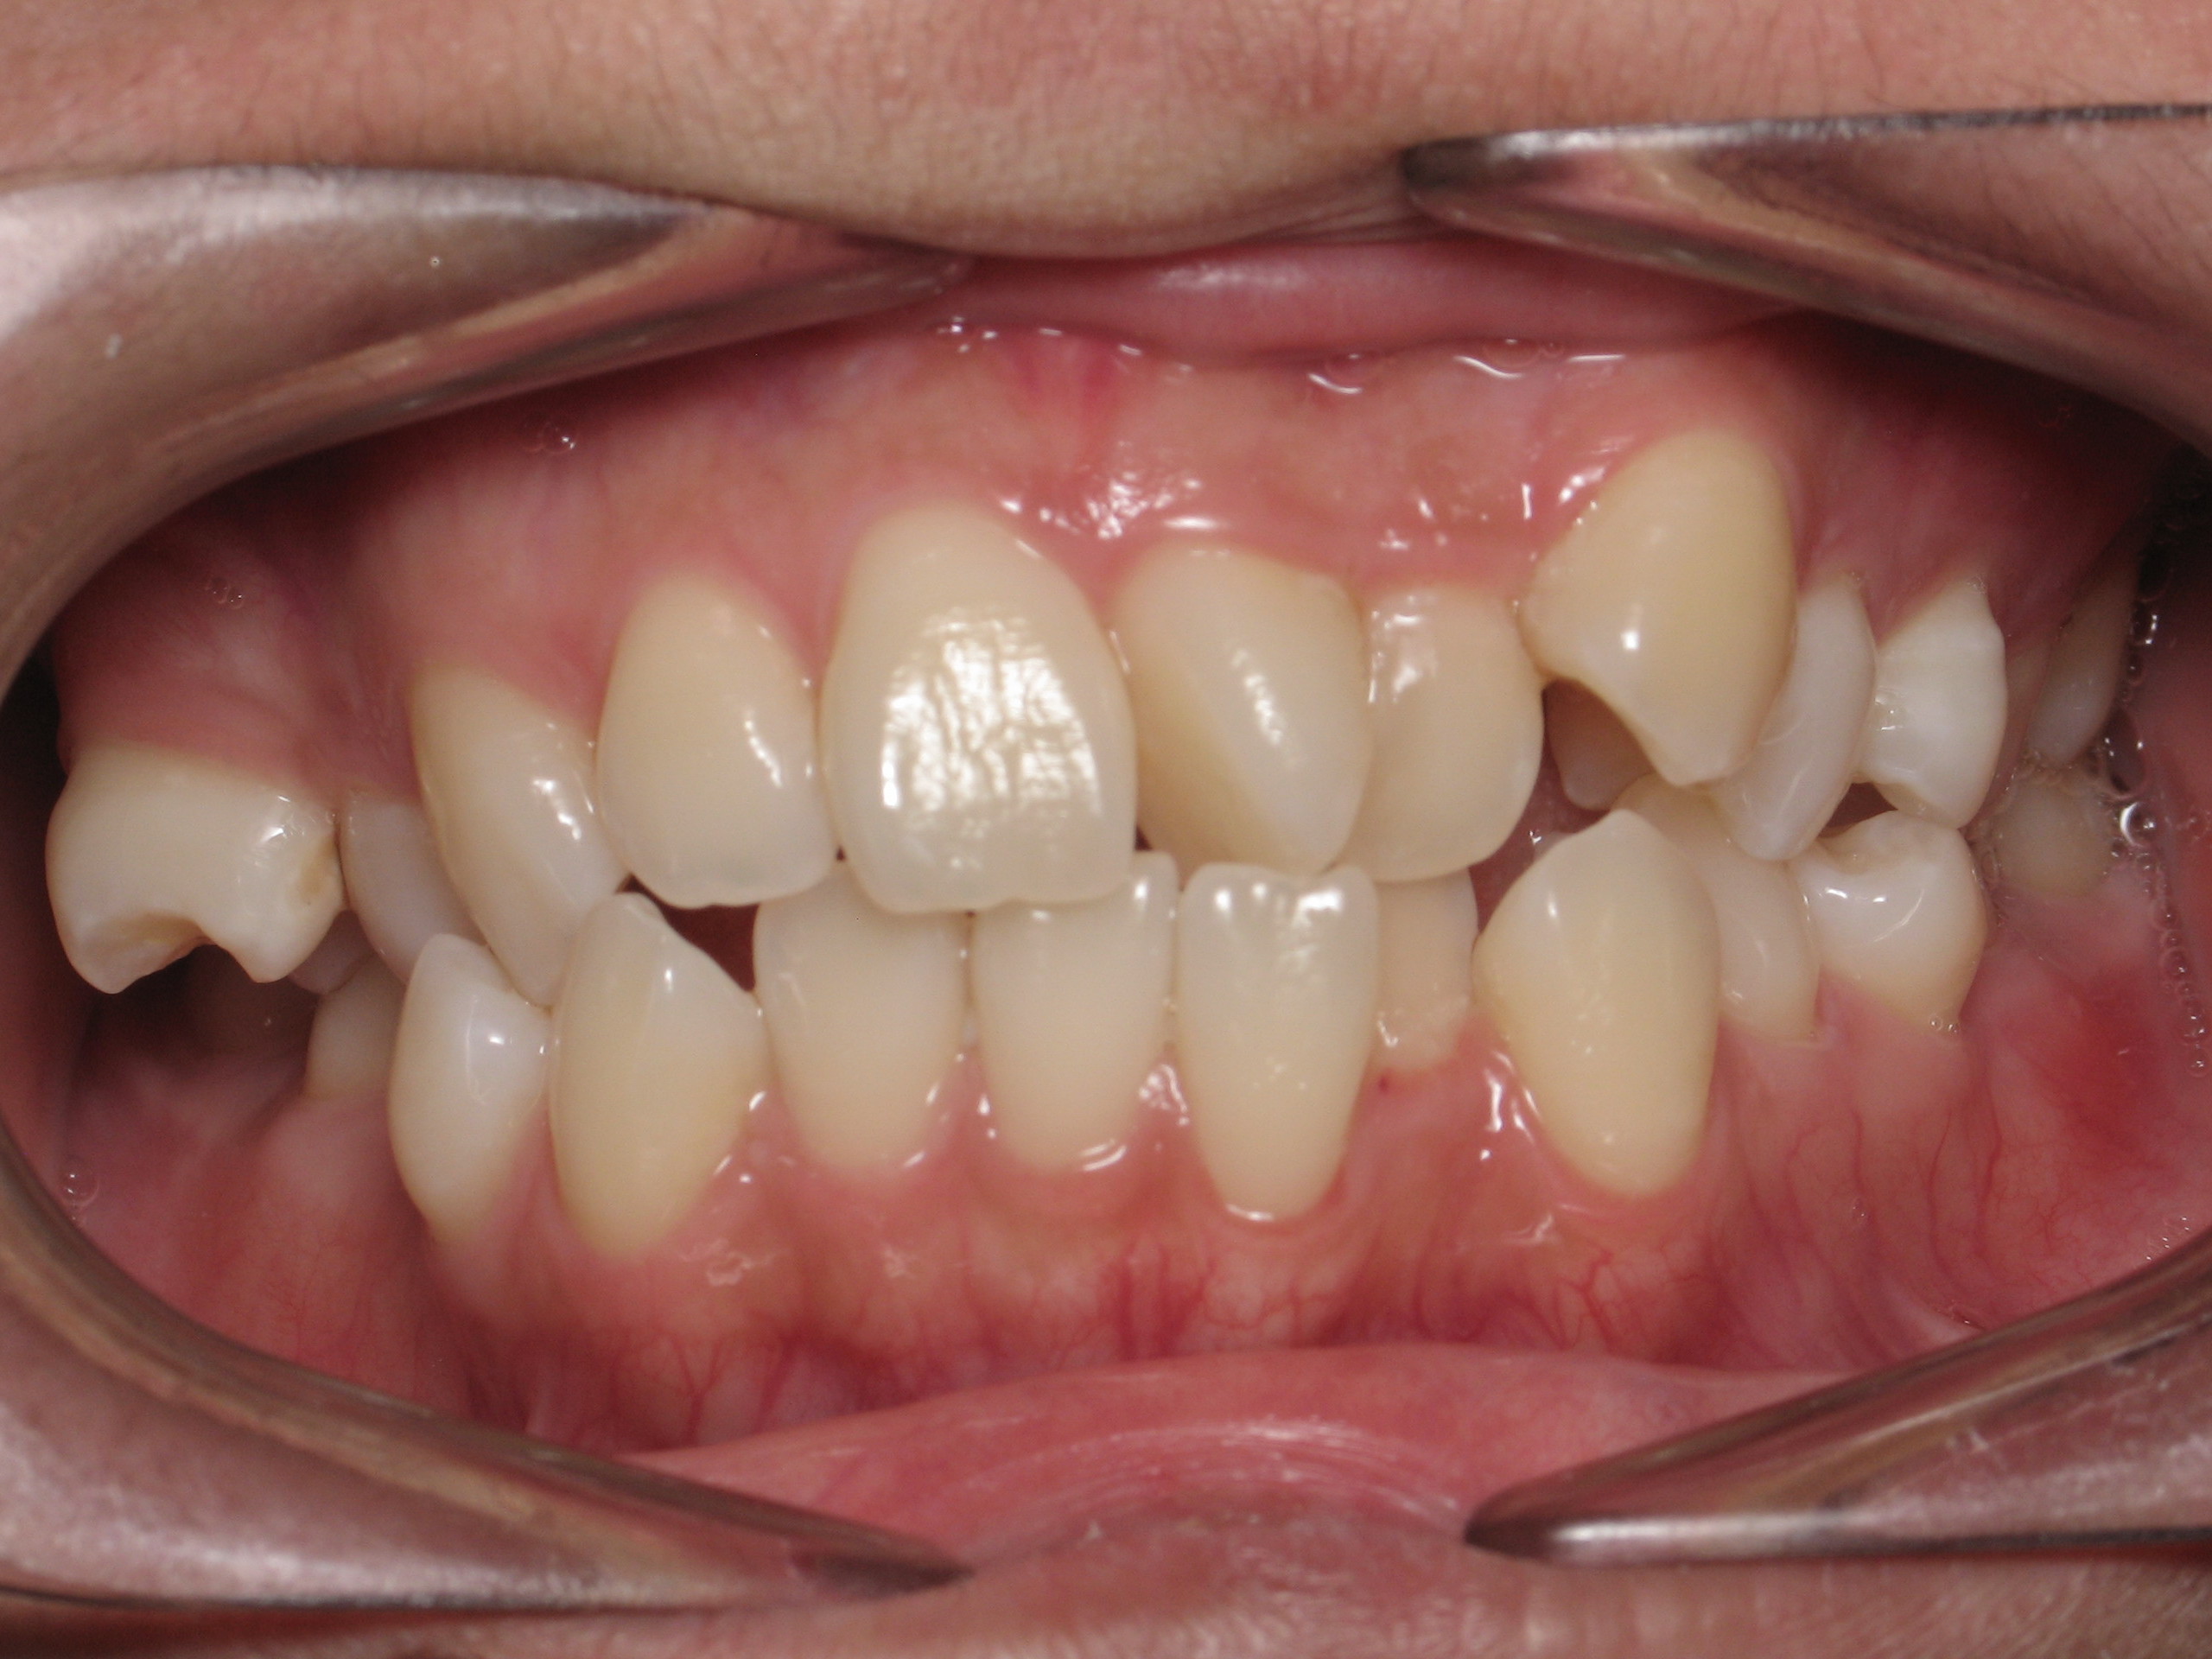

Orthodontic Treatment X-ray - Before

After Series of Teeth Extractions, Upper Left Canine Unerupted.

Ready to Start Ortho Treatment